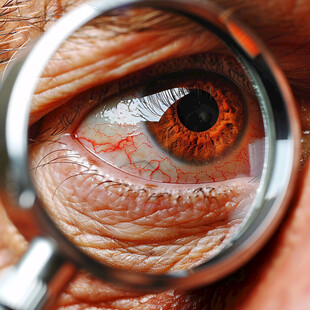

巩膜 有序 健康保健 商用作品

巩膜 有序 健康保健 商用作品 -